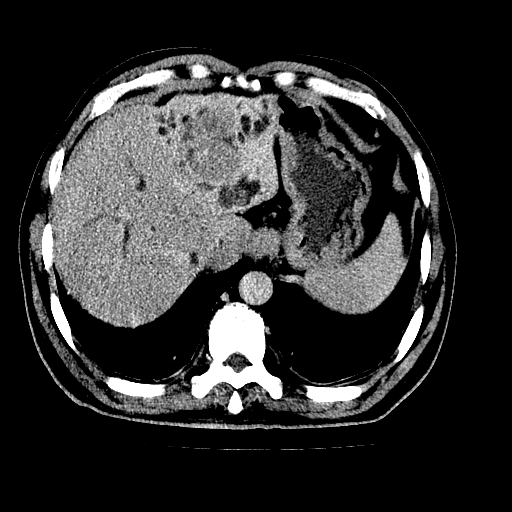

男,66岁,上腹部不适、黄染一周。彩超示:肝左叶占位,肝内胆管扩张,胆总管扩张,胆总管占位?

肝左叶不规则软组织肿块影,边缘不规整邻近肝实质受累分界不清;肝内胆管(左叶)明显扩张成“软藤状”,诊断:肝左叶胆管细胞癌。

肝左叶不规则软组织肿块影,边缘不规整邻近肝实质受累分界不清;肝内胆管(左叶)明显扩张成“软藤状”,诊断:肝左叶胆管细胞癌。胆囊钙乳症。

胆囊缩小,其内胆汁浓缩,也提示梗阻部位应该位于胆囊管起始部以上或是胆囊管受累及,支持肝外胆管癌。